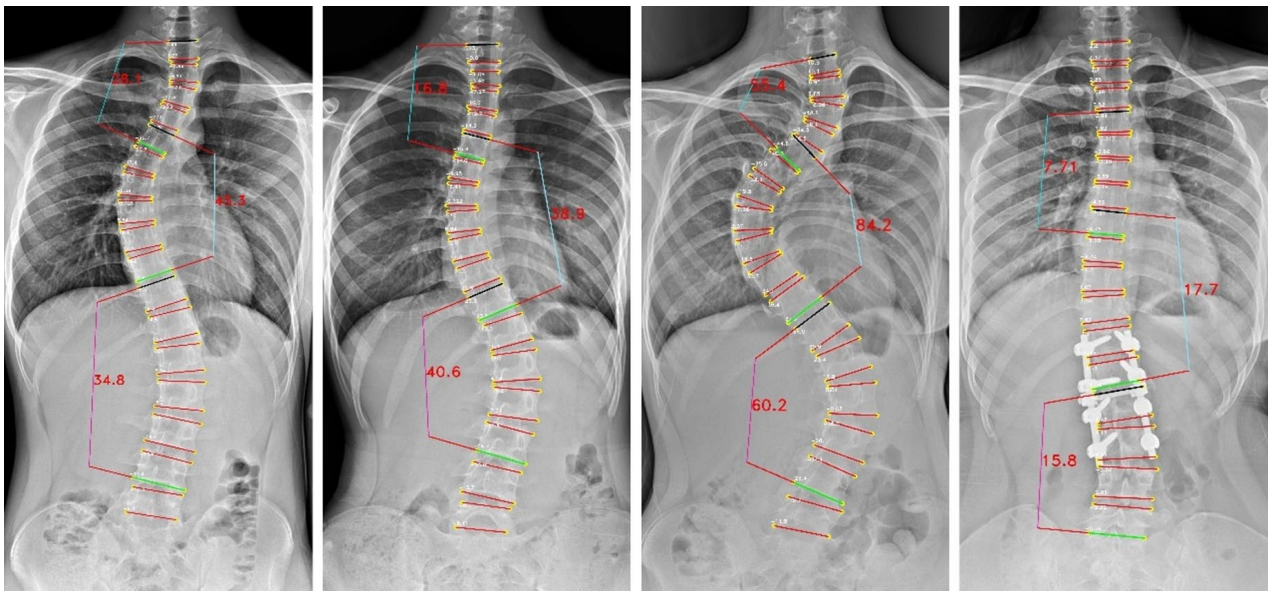

Cobb角是評估脊柱側彎程度的"金標準",其測量結果可以用於評估病情、制定治療計劃和跟蹤疾病進展。萬東Cobb角自動測量系統,1秒內即可完成Cobb角計算,較傳統手工測量(耗時>2 分鐘)效率提升百倍。經研究驗證,Cobb角平均測量誤差僅3.918°,ICC爲0.943,驗證了該算法技術指標頂尖、誤差小、重複性極好,相關論文收錄於脊柱外科和脊柱研究領域的國際頂級期刊之一《European Spine Journal》。

The Pearson correlation only on major Cobb angle of AP view images

The vertebrae four corner points and the Cobb angles measurement for AP view images

The vertebrae four corner points and the Cobb angles measurement for LAT view images

基於負重位CBCT的全脊柱三維Cobb角自動測量,實現了椎體的高精度自動分割,其Dice係數達0.9776(自動分割的結果越準確,Dice值就越接近1),誤差極小;三維Cobb角測量可接受度>97.05%,關鍵椎體識別準確率98.53%,顯著優於傳統方法。基於負重位CBCT椎體軸向旋轉角度自動測量,與人工測量一致性ICC 達0.76,誤差控制在±3.04° 內,實現了對椎體旋轉的客觀、高效、可重複測量,一鍵自動生成,高效助力臨牀精準診療。該研究入選中華醫學會放射學學術大會(CCR 2025)。